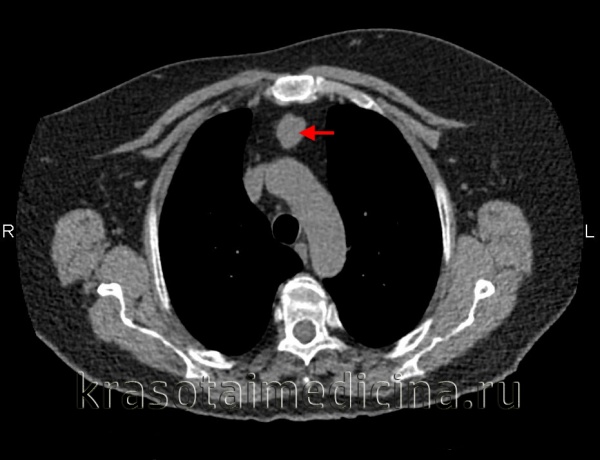

В верхнем средостении чаще всего обнаруживаются тимомы, лимфомы и загрудинный зоб; в переднем средостении - мезенхимальные опухоли, тимомы, лимфомы, тератомы; в среднем средостении - бронхогенные и перикардиальные кисты, лимфомы; в заднем средостении - энтерогенные кисты и неврогенные опухоли.